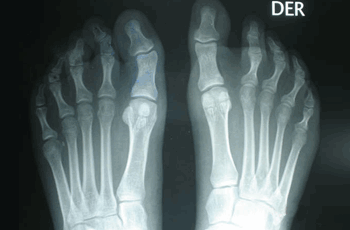

Caso 2: Hallux Valgus del Adolescente

Pie Izquierdo operado